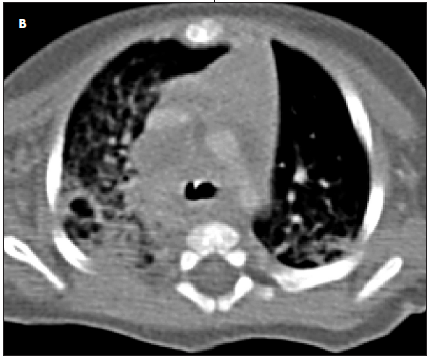

Results of a complete blood cell count showed lymphocyte predominance. Results of a basic metabolic panel were normal. The C-reactive protein level was 6.7 mg/L; erythrocyte sedimentation rate, 8 mm/h; hemoglobin level, 9.6 g/dL; and hematocrit, 29%. Polymerase chain reaction (PCR) testing was positive for Cytomegalovirus and negative for Toxoplasma, HIV, Epstein-Barr virus, and respiratory syncytial virus. A chest radiograph showed a hyperinflated right lung with a shift of the mediastinal contents into the left hemithorax, suggestive of air trapping and consolidation in the right upper lobe and hilar region (A); there was no thymic shadow. A CT scan of the chest showed diffuse mediastinal and right hilar adenopathy (B); this caused partial compression of the right main-stem bronchus. MRI showed bilateral pleural effusion with hilar lymphadenopathy and mediastinitis.